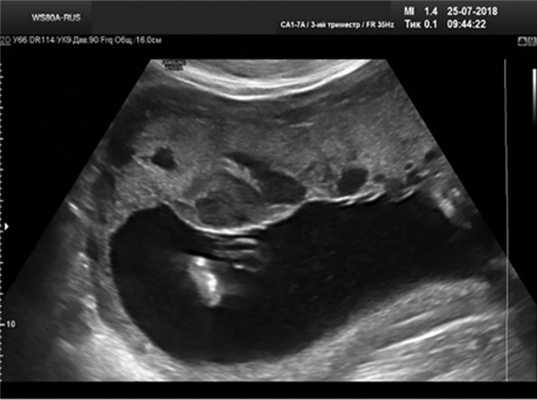

В подгруппу 1В были отнесены 26 пациенток со значительными структурными изменениями (рис. 4) в плаценте (расширение МВП более 20 мм и менее ⅓ плаценты).

Рис. 4. Значительные расширения МВП плаценты.

В этой подгруппе (см. рис. 1) среди экстрагенитальной патологии выявлены СД в 11 (42,3%) наблюдениях, обострение ВПГ-инфекции — у 1 (3,8%) пациентки.

У 6 пациенток в группе 1В беременность была повторной. Все имели осложнения предыдущей беременности: отслойку плаценты и экстренное кесарево сечение (2), преждевременные оперативные роды в 36 нед по поводу тяжелой преэклампсии (1), антенатальную гибель плода (1), невынашивание беременности (2), т.е. в половине наблюдений в этой подгруппе предыдущая беременность закончилась фатальными осложнениями. Во время данной беременности у 1 пациентки произошла отслойка плаценты, у 1 выявлен СЗРП III степени, и в 2 наблюдениях обнаружены критические показатели плодового кровотока в начале III триместра, что потребовало экстренного досрочного родоразрешения.

Среди 26 пациенток не обследованы на генетические маркеры тромбофилии 11 (42,3%), в 2 (7,7%) наблюдениях носительство генов тромбофилии не подтверждено, в 11 (42,3%) наблюдениях выявлена сочетанная тромбофилия, в 2 (7,7%) наблюдениях — PAI I. Чувствительность признака составила 87%, доля ложноположительных диагнозов —13%.